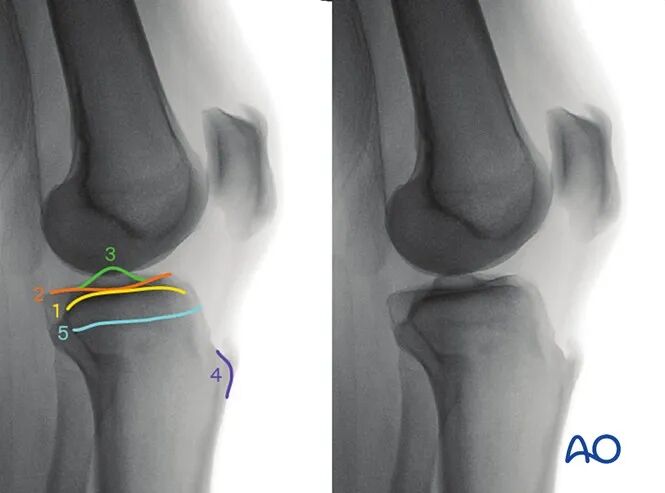

5. 评估外侧胫骨平台的改良侧位

最佳体位摆放要求

以标准侧位为基础体位,

将患侧下肢外展约10°-20°。

最佳影像的验证标准

满足以下条件即为评估外侧胫骨平台的最佳改良侧位影像:

●外侧胫骨平台的凸面轮廓在关节间隙内清晰显示,且位于内侧胫骨平台凹面的头侧;

●外侧胫骨平台居中显示于影像屏幕。

可识别的解剖标志与线条

该体位下可识别的解剖标志与线条为:

外侧胫骨平台。

临床观察要点

该体位尤其适用于判断以下情况:

●关节面不平整;

●植入物穿入关节腔。

6. 评估内侧胫骨平台的改良侧位

将患侧下肢内收约10°-20°。

满足以下条件即为评估内侧胫骨平台的最佳改良侧位影像:

●内侧胫骨平台的凹面轮廓在关节间隙内清晰显示,且位于外侧胫骨平台凸面的头侧;

●内侧胫骨平台居中显示于影像屏幕。

内侧胫骨平台。